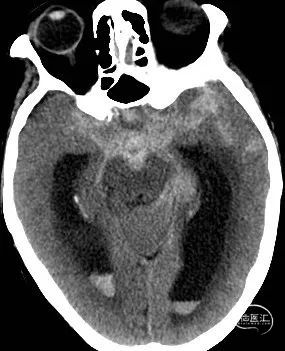

影像检查:CT提示广泛蛛网膜下腔出血(环池、鞍上池、桥前池、侧裂池、侧脑室),Fisher分级3级。CTA提示右侧颈内动脉交通段动脉瘤。

术前CT

术前DSA、DSA 3D